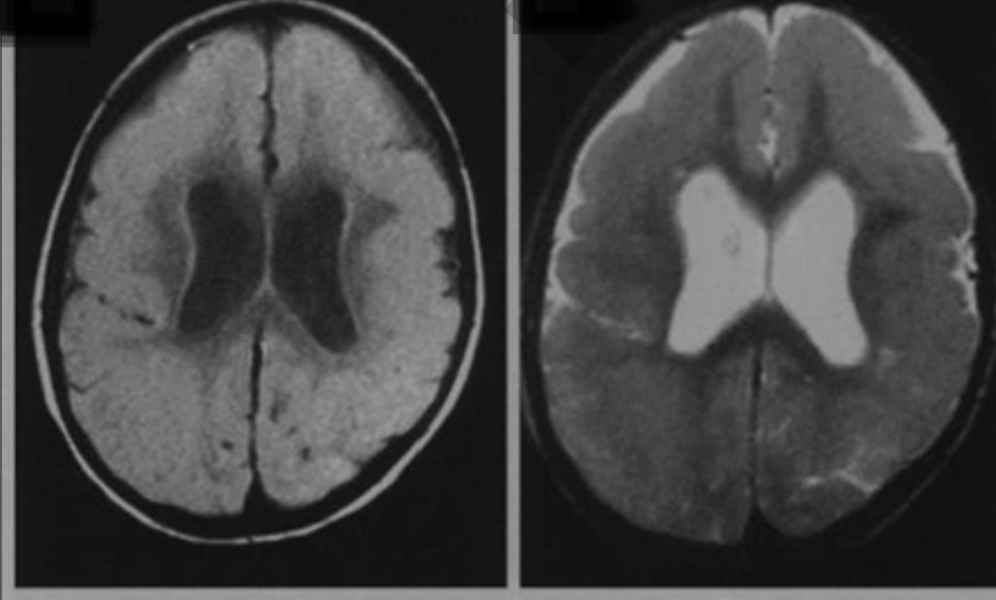

а) субэпендимарная гетеротопия серого вещества в виде очагов последнего по краю боковых желудочков мозга с фестончатостью их контура b) субкортикальная гетеротопия (см. ниже) и киста прозрачной перегородки